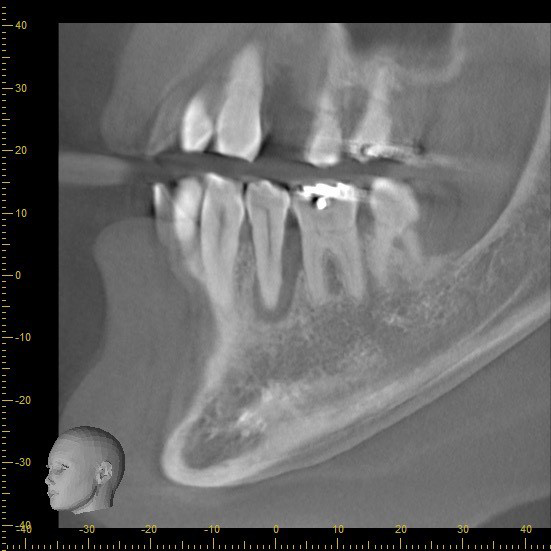

この部分をCTでみてみると、骨の壁がほとんどなくこのままにしておくと、他の歯と同じように自然に抜けてしまう未来が見えます。

先生によっては、抜歯宣告を受けてもおかしくないくらい状態は悪いです。